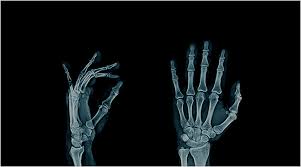

골관절염은 무릎 연골의 손상으로 인해 발생하는 만성적인 관절 질환입니다. 인간에게 매우 중요한 질환 중 하나입니다. 이를 이해하려면 먼저 무릎 관절의 구조를 알아야 합니다. 무릎 관절은 허벅지의 대퇴골, 다리의 정강이뼈인 경골 슬개골로 구성되어 있습니다. 경골을 보조하는 비골도 포함됩니다. 이 뼈들은 관절낭으로 둘러싸여 안정성을 유지합니다. 그러나 무릎은 뼈와 뼈의 접합 부분이 얕아 불안정해지기 쉬운 구조를 가지고 있습니다. 이를 보완하기 위해 주변의 근육, 인대, 힘줄이 관절의 안정성을 유지하는 역할을 합니다. 무릎 관절의 연골은 뼈와 뼈가 직접 맞닿는 것을 방지해주는 쿠션 역할을 하며 충격을 흡수하는 데 중요한 역할을 합니다. 하지만 연골은 시간이 지남에 따라 자연스럽게 마모되며 한 번 손상되면 재생되지 않습니다. 근력이 약해지면 연골의 마모가 더 빠르게 진행되어 골관절염의 원인이 됩니다. 연골이 손상되면 무릎 통증이 발생하고, 이로 인해 보행이 힘들어지는 등 일상생활에 큰 영향을 미칠 수 있습니다. 과체중은 무릎에 더 큰 부하를 주어 연골 마모를 가속화하는 주요 요인으로 알려져 있습니다. 그러나 과체중이 아닌 사람도 골관절염에 걸릴 수 있으며 연골의 마모는 다양한 요인에 의해 발생할 수 있습니다.